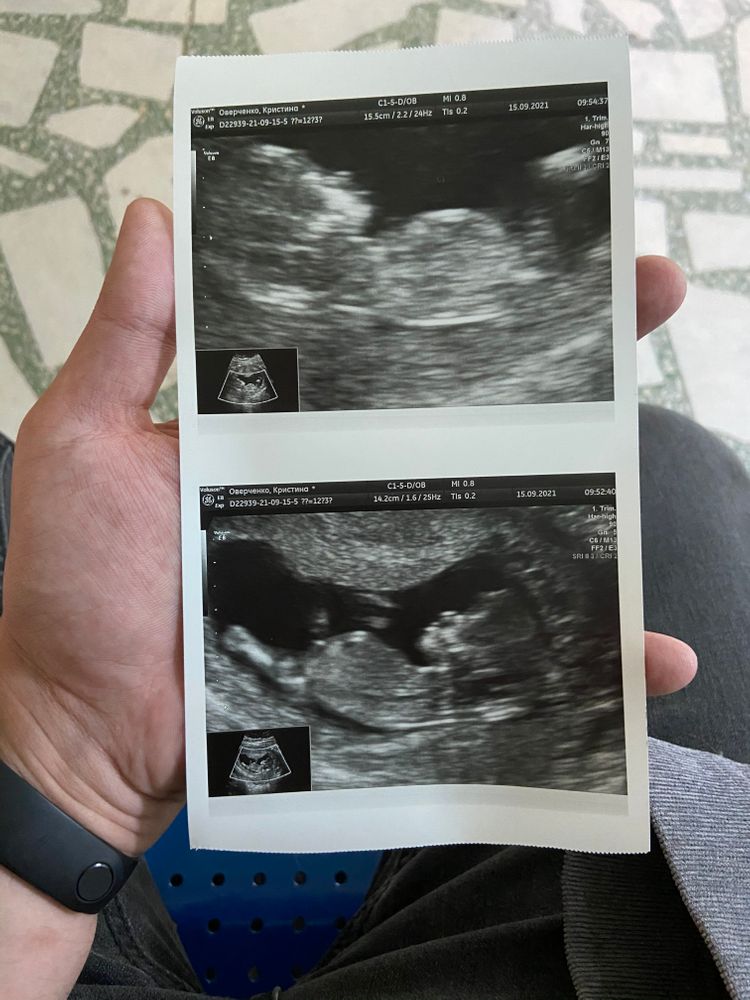

Кристина в Благополучная беременность 4 года Какой пол? Пол малыша Добрый вечер, кто-то разбирается какой пол? Посмотрите еще 20 записей на эту тему Отменить Ответить Юлия Вроде по углу девочка 10.01.2022 Ответить Юлия Sonnце Девочка. 26.09.2021 Ответить Жаркое Лето Не очень видно. Чисто по профилю поставлю на мальчика 26.09.2021 Ответить Виктория Девчулечка 💝! 26.09.2021 Ответить Таня Девочка 26.09.2021 Ответить Настя Литвинова Девочка 26.09.2021 Ответить Елена Девочка 26.09.2021 Ответить Мечты сбываются Не видно бугорок 25.09.2021 Ответить ленчик Мне кажется мальчуля там у вас 🤗🤗 25.09.2021 Ответить Луиза Парфенова Мне кажется мальчик)) 25.09.2021 Ответить Оставшиеся комментарии доступны после регистрации Зарегистрируйтесь и получите полный доступ ко всем функциям сайта. Зарегистрироваться Девочки HELP! Мальчик или девочка все таки ? Гендер-Пати Чаты Беременных Выберите чат: Январята-2026 Февралята-2026 Мартята-2026 Апрелята-2026 Майчата-2026 Июнята-2026 Июлята-2026 Августята-2026